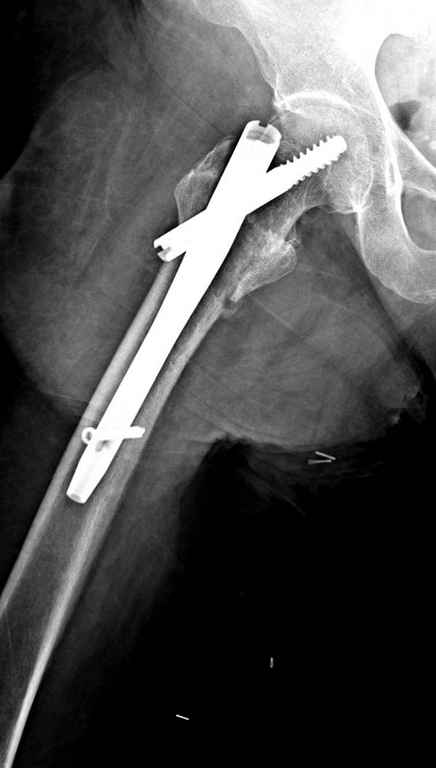

Вашему вниманию представляется похожий случай, пациентке 70, осложнился в течение одного месяца после операции. Ревизия с заменой сустава, кабельная фиксация на трохантер. При установке в дистальном диафизе обнаружен тонкий кортикальный слой и сделана профилактика от возможного перелома аллографтом.

Перечисляя различные техники, хотел бы напомнить, что современный ортопед обязан владеть всеми видами фиксации, включая сложные с обнажением фокуса перелома.